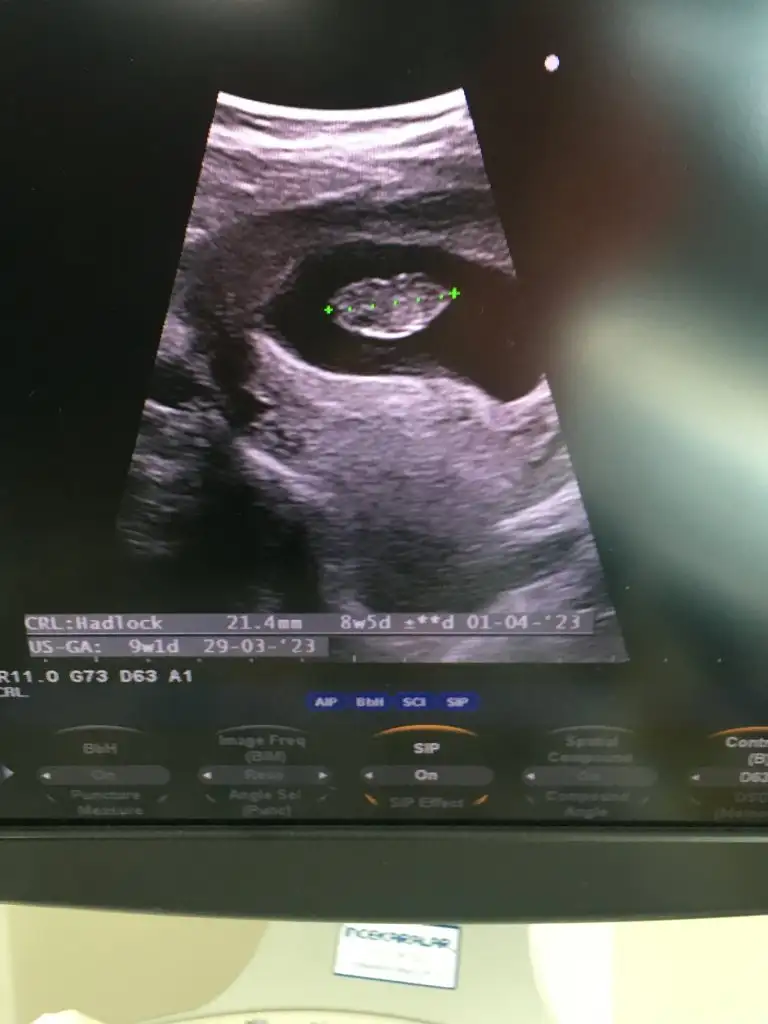

Bana da bak lütfen karından ultrason bu ve 11+2 günlük

NurSu-14Ocak .!.:Ustteki 9 haftalik

Altakki 8 haftalik